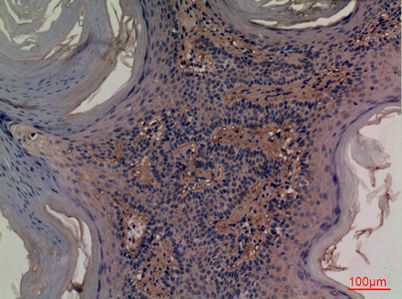

Product name: CD73 rabbit pAb

Dilutions: Western Blot: 1/500 - 1/2000. IHC-p: 1:100-300 ELISA: 1/20000. Not yet tested in other applications.

Immunogen: The antiserum was produced against synthesized peptide derived from the Internal region of human NT5E. AA range:431-480

Background: The protein encoded by this gene is a plasma membrane protein that catalyzes the conversion of extracellular nucleotides to membrane-permeable nucleosides. The encoded protein is used as a determinant of lymphocyte differentiation. Defects in this gene can lead to the calcification of joints and arteries. Two transcript variants encoding different isoforms have been found for this gene.[provided by RefSeq, Mar 2011],